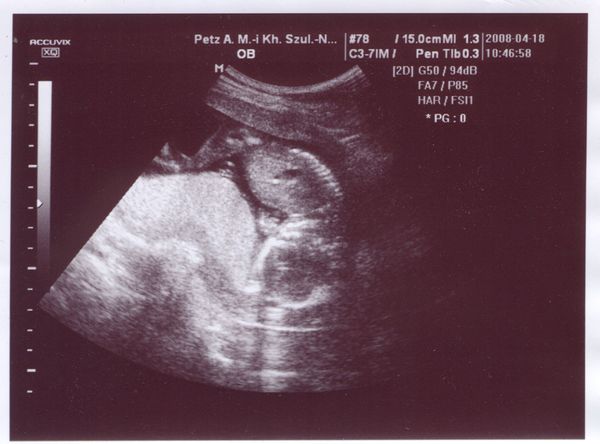

Mindenkinek nagy gratula akik már tudják a baba nemét, valamint nagyon jók a képek! Én még nem tudom, de nagyon kíváncsi vagyok ki lakik odabennt. Jövő hét pénteken megyek védőnőhöz, akkor meglesz az AFP eredményem is, szerintem utána való héten megyek genetikai UH-ra, ott rákérdezek.

Most írta valamelyikőtök, kipróbáltam a cérnára tett gyűrűt, hát, kislány jött ki. Aminek nagyon örülnék, mert az a vágyam elsőre. A kínai szerint is kislány, de azt bocsi, de hülyeségnek tartom a fent leírtak miatt. Bár még kb. 15 éve azt jósolták, hogy először egy fiam, aztán egy lányom lesz, és a hasam elég fiús, így kíváncsian várom az UH-ot.

Gratula a félidőd+1 napodhoz!! Mi ma vagyunk 18 hetesek, azaz 4 hónaposak, ugyanis napra pontosan 5 hónap múlva kellene elvileg szülnöm. De ezt majd a babó eldönti.